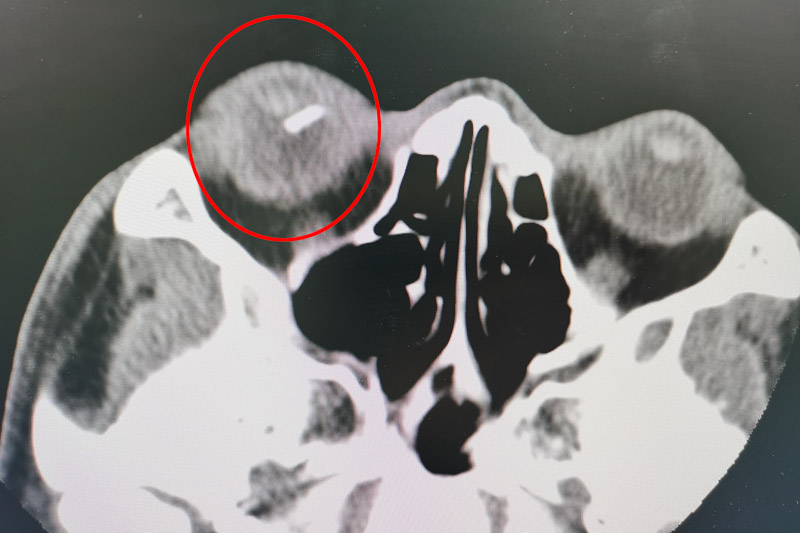

經(jīng)檢查,發(fā)現(xiàn)患者右眼眼球已被穿通,眼球內(nèi)還殘留有玻璃體異物,目前患者視物不清,只有光感,情況十分危急。眼科團隊針對該患者的情況立刻開展了術(shù)前討論,一致認為可以通過玻璃體切割術(shù)清除玻璃體內(nèi)的積血及機化組織并摘除異物,保住患者的眼球及視力。

但該眼內(nèi)手術(shù)難度很大,稍有不慎就可能出現(xiàn)眼內(nèi)出血、眼內(nèi)感染、玻璃片術(shù)中再次掉落損傷視網(wǎng)膜甚至黃斑部的風(fēng)險。為確保手術(shù)萬無一失,眼科團隊做了詳細、周密的術(shù)前準備。術(shù)中使用微創(chuàng)23G玻璃體切割系統(tǒng),在眼球上建立直徑為毫米級別的套管通道,使用顯微器械進行手術(shù)處理。通過顯微鏡可以看到視網(wǎng)膜上亮晶晶的玻璃碎片,玻璃碎片表面光滑,大小是手術(shù)切口的十倍左右。施術(shù)者小心翼翼從碎片兩側(cè)頭端、側(cè)面輕輕翻開嘗試夾取,稍有不慎,就會損傷視網(wǎng)膜,造成二次傷害。最終憑借高超的技巧,將長1.4cm的玻璃碎片成功取出,保住了患者的眼球。